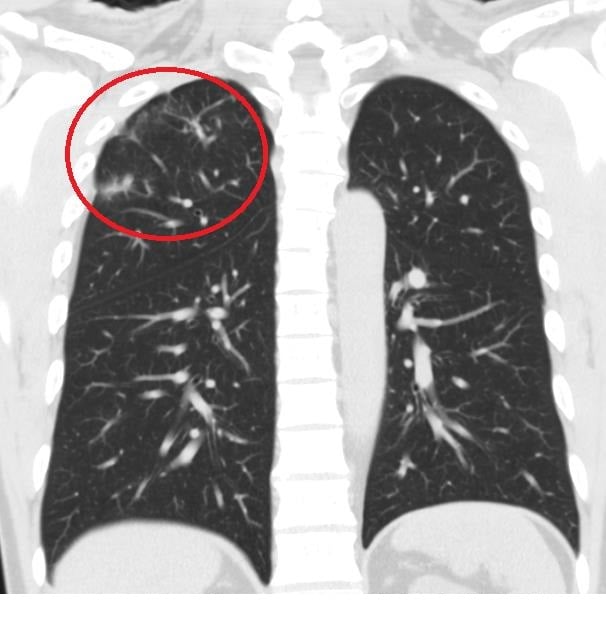

▲放射檢查可見經治療後肺部病灶已明顯改善。

胸腔內科醫師莊子逸強調,肺結核若能及早診斷並規律服藥,多數患者皆可有效治癒。該院透過精準的結核菌PCR分子診斷技術,搭配標準化藥物治療流程,不僅提升診斷準確度與治療成功率,也有助縮短病程並降低傳染風險。

臺中榮總灣橋分院長期致力於守護雲嘉南地區民眾的肺部健康。莊醫師提醒,若出現長期咳嗽、不明原因發燒、體重減輕或呼吸困難等症狀,應儘早至胸腔內科門診檢查,避免延誤診斷。透過精密儀器與專業團隊的早期介入治療,許多患者都能如李先生一般,重新找回暢快呼吸的權利,迎向健康人生。(圖:劉芳妃翻攝)